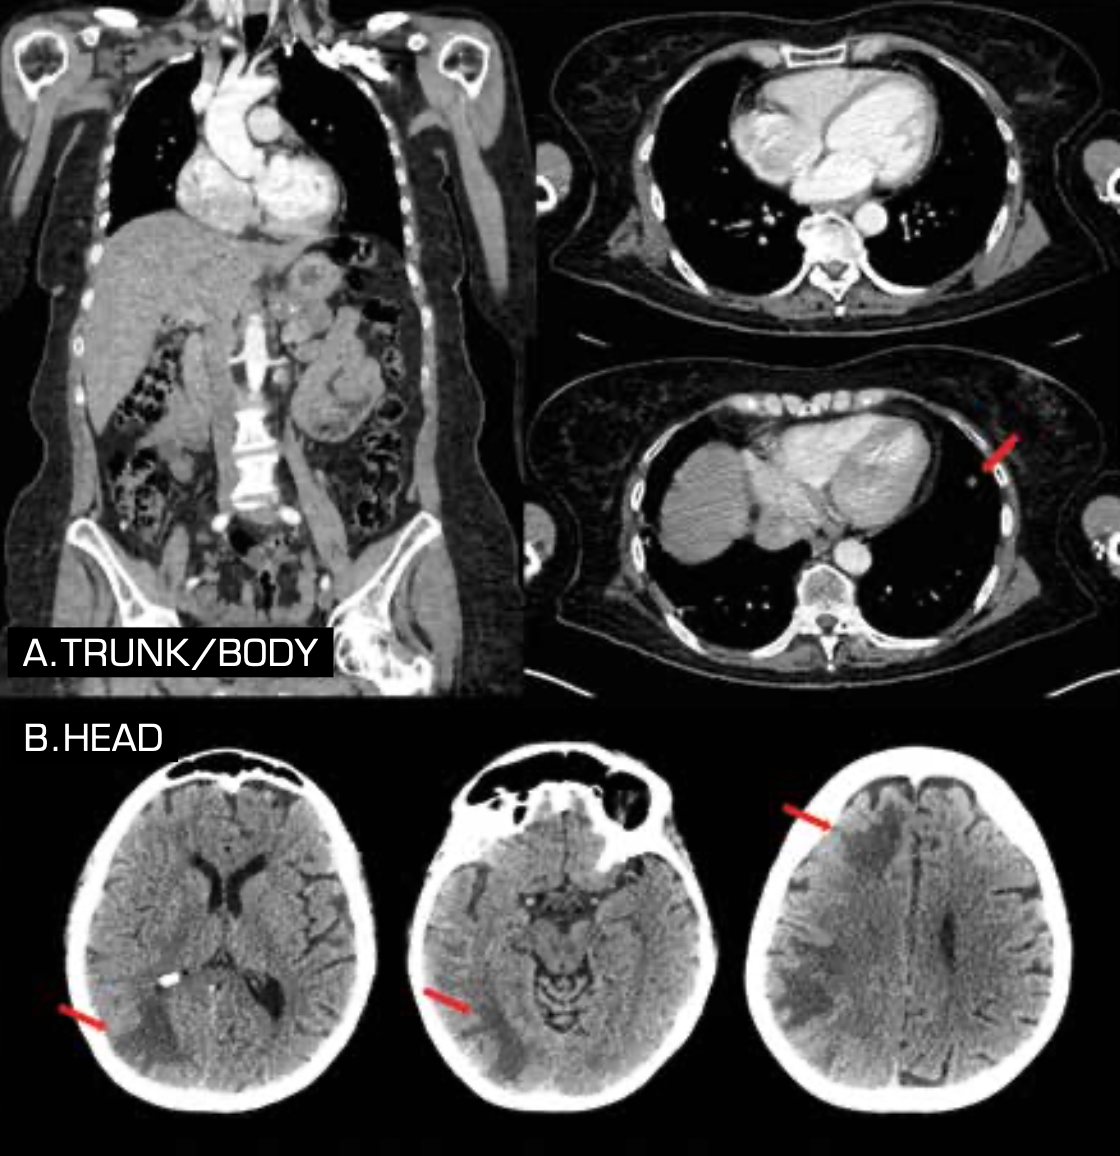

In 2017, multiple lung and pancreatic metastases were detected in a follow-up PET scan. A brain MRI was performed; no evidence of disease was found. A BRAF V600E mutation was documented. Treatment with nivolumab (Opdivo) was started. After 9 months of treatment, progression of disease to soft tissue, myocardium, pericardium, lung, pancreas, left adrenal gland, and bone was documented (Figure 1). Treatment with dabrafenib (Tafinlar) plus trametinib (Mekinist; D+T) was started. A reduction of the tumor burden was achieved after 2 months of treatment, and after 6 months, the patient had a deep partial response of more than 80% reduction of the tumor load. After 1 year of treatment, the patient came to the clinic with neurological symptoms. A brain CT scan revealed multiple supratentorial lesions, with the largest, measuring 23 mm, localized in the parietooccipital region. Other lesions, each measuring less than 1 cm, were localized in the right parietal region, frontal region, and left parietal lobe (Figure 2A). A CT scan ruled out progressive disease in other sites (Figure 2B).

FIGURE 2. Follow-up CT scan (A) after 1 year of dabrafenib plus trametinib shows partial response in lung and pancreatic lesions and complete response in myocardium and mediastinum. Brain CT scan (B) shows multiple supratentorial lesions with associated edema.